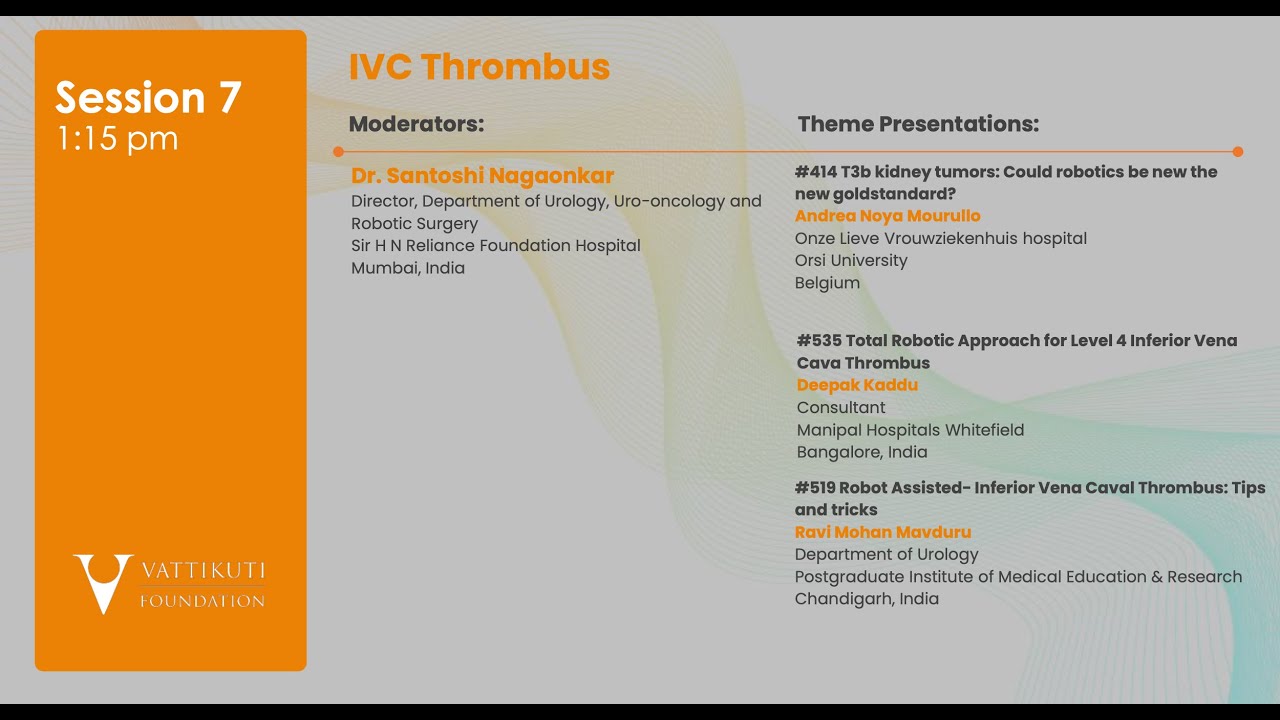

Jaipur Saturday Session 7 IVC Thrombus

Humans of Robotic Surgery, KS Awards, Robotics, Surgeon, Video Library ';